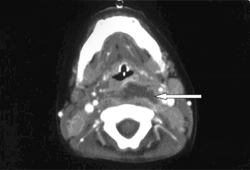

Retropharyngeal abscess

CT scan of neck demonstrating ring-enhancing lesion

Philpott CM, Selvadurai D, Banerjee AR. Paediatric retropharyngeal abscess. J Laryngol Otol. 2004;118:919-926